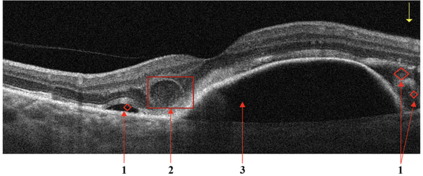

Optical coherence tomography (OCT) is a non-invasive imaging technique with extensive clinical applications in ophthalmology. OCT enables the visualization of the retinal layers, playing a vital role in the early detection and monitoring of retinal diseases. OCT uses the principle of light wave interference to create detailed images of the retinal microstructures, making it a valuable tool for diagnosing ocular conditions. This work presents an open-access OCT dataset (OCTDL) comprising over 1600 high-resolution OCT images labeled according to disease group and retinal pathology. The dataset consists of OCT records of patients with Age-related Macular Degeneration (AMD), Diabetic Macular Edema (DME), Epiretinal Membrane (ERM), Retinal Artery Occlusion (RAO), Retinal Vein Occlusion (RVO), and Vitreomacular Interface Disease (VID). The images were acquired with an Optovue Avanti RTVue XR using raster scanning protocols with dynamic scan length and image resolution. Each retinal b-scan was acquired by centering on the fovea and interpreted and cataloged by an experienced retinal specialist. In this work, we applied Deep Learning classification techniques to this new open-access dataset.